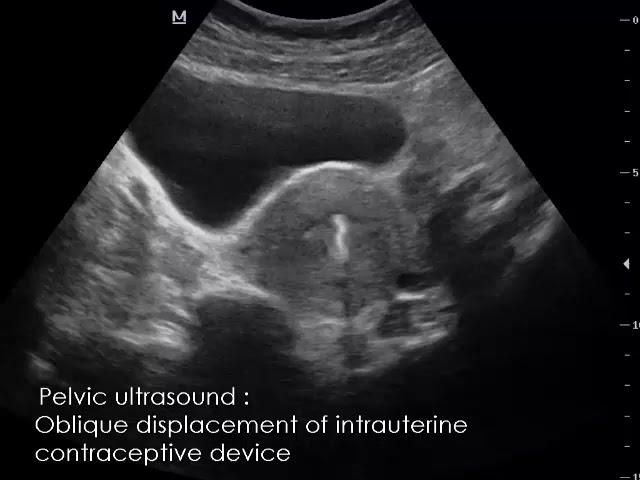

CASE 780 Oblique displacement of intrauterine contraceptive device